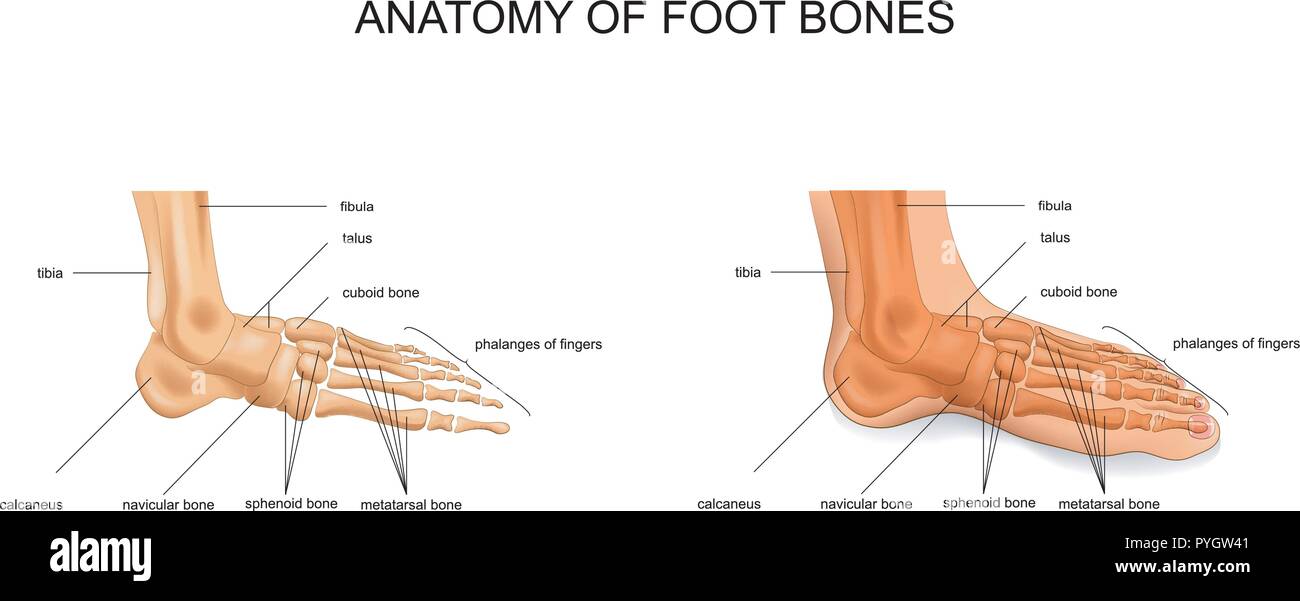

RF2DHMD0H–OS du pied. Anatomie humaine. Le schéma montre l'emplacement et le nom de tous les os du pied.

RF2WWY5XN–Os du pied humain avec le nom et la description de tous les sites. Vue supérieure. Anatomie humaine. Illustration vectorielle isolée sur un fond blanc.

RF2WNN754–Illustration médicale des principales parties des os du pied en vue antérieure, avec annotations.

RF2J65WT4–Anatomie du pied. Pied humain avec le nom et la description de tous les os et sites. Vue de dessus et vue latérale. Arcs des pieds. Anatomie du squelette. Vecteur

RF2R3WKY1–Illustration médicale des principales parties des os du pied en vue latérale, avec annotations.